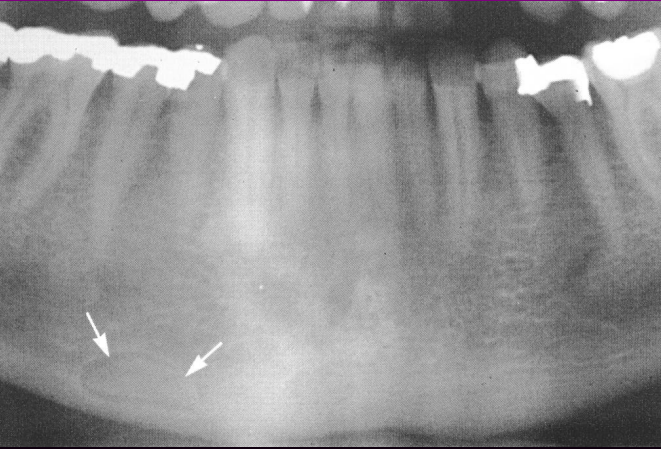

• Representa 1% dos tumores odontogênicos.

Origina-se dos cementoblastos. 50% afetam os 1º molares permanentes. Raro em dentes decíduos.

• Mais comum na mandíbula (80%), com maior incidência na região de molares e prémolares(90%).

Metade dos casos envolve

primeiro molar

Cementoblastoma Radiografia ?

* 2/3 dos pacientes apresentam dor intermitente de baixa intensidade e tumefação local. * Massa radiopaca que se funde a raiz de um ou mais dentes, circundada por fina halo radiotransparente. Contorno da raiz é perdido. *Fusão com a raiz do dente envolvido.